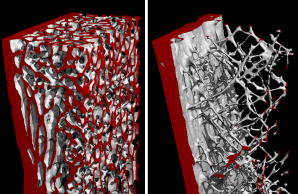

Project 4: Molecular bases of non-classical osteogenesis imperfecta

Project 4 focuses on the non-classical forms of osteogenesis imperfecta, which are characterized by low bone mass and skeletal fragility. We want to better understand the dynamic molecular processes during bone formation as well as identify key molecules and signaling pathways under pathophysiological conditions in order to establish causal therapies.